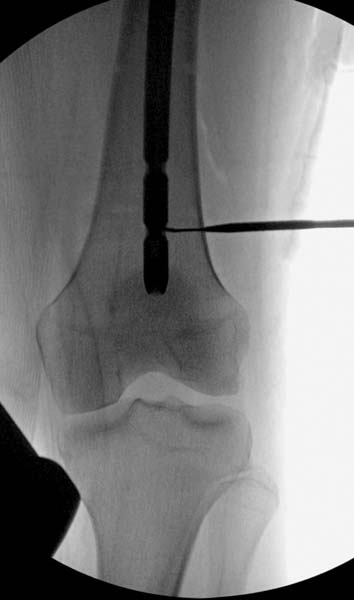

> стабильная.. На третьий день провели стабилизацию перелома бедра

> антеградным остеосинтезом.

> Закрытый БИОС решает множественные проблемы связанные с лечением

> переломов, но проблема дистальной блокировки без рентгена до сих пор

> остается нерешенной. Рекламированные производителями приспособления для

> дистальной блокировки из-за различной кривизны кости не эффективны или

> стоит очень дорого (Smith&Nephew SureLock). Задержка операции из-за

> блокировки не всегда удовлетворяет, и многих вынуждает искать

> альтернативные методы фиксации. С результатами таких действий,

> остеомиелитом и несращениями, встречаемся в ежедневной жизни..